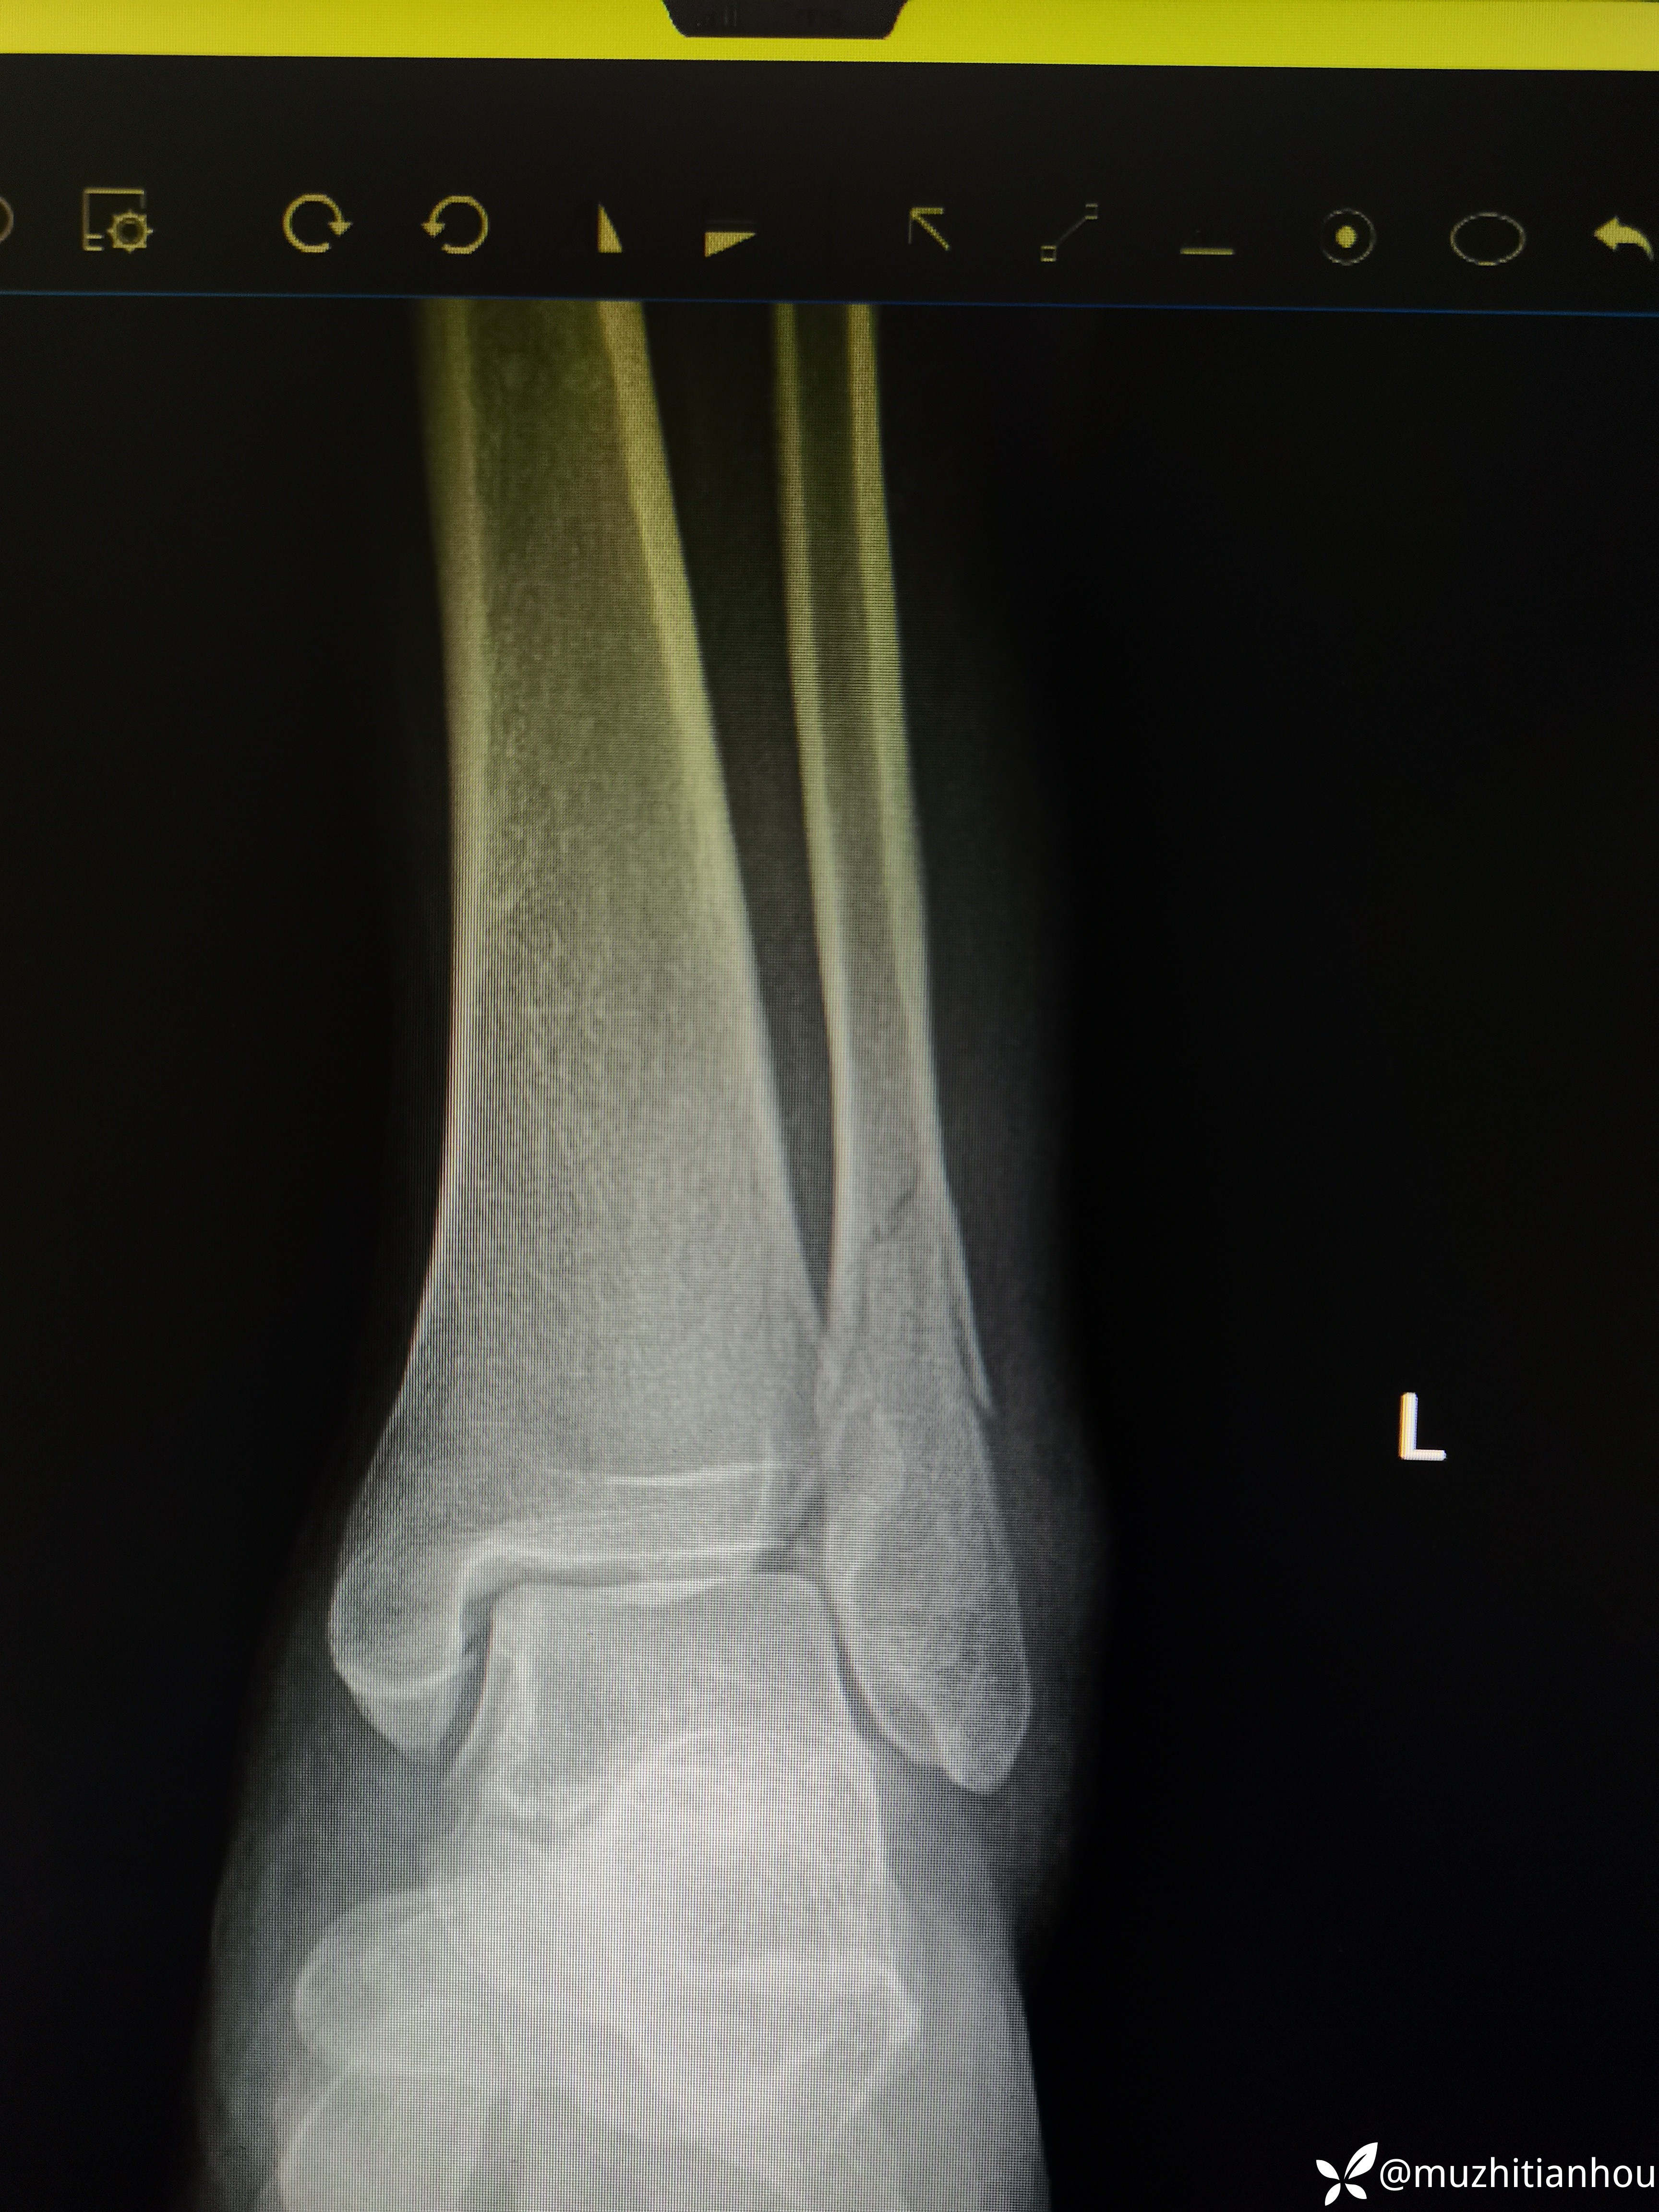

58岁中年女性,扭伤左踝关节肿痛活动受限2小时来诊。拍片是左踝关节骨折(SER 四度损伤?),患者门诊要求保守治疗,跟其讲明踝关节骨折属于毫米级手术,四度的损伤预示着踝关节的不稳,容易产生骨折再次移位,踝穴不匹配等并发症,而且没有CT进一步评估,对下胫腓是否存在Tilaux骨块和或后踝Volkman骨块无法评估,种种不确定因素预示着保守治疗并发创伤性关节痛可能性较大,建议住院进一步评估,积极手术治疗,患者及家属同意入院完善CT检查确定指征明确,准备择期手术。术后待奉上。

返回头来我们再阅片发现正位下胫腓存在骨块,存在分离移位,内踝侧位片骨折线前上后下亦存在分离移位,虽然腓骨长度没问题,但凭借这两处骨折和四度损伤样也完全说明手术指征明确。

看着腓骨长度没问题,旋转没问题,踝穴也可以,这个岁数是不是可以保守的?

侧位没经验的大夫会不会看内踝呢?有什么端倪吗?门诊碰到这样的患者问你能不能保守治疗,你会怎么处理?